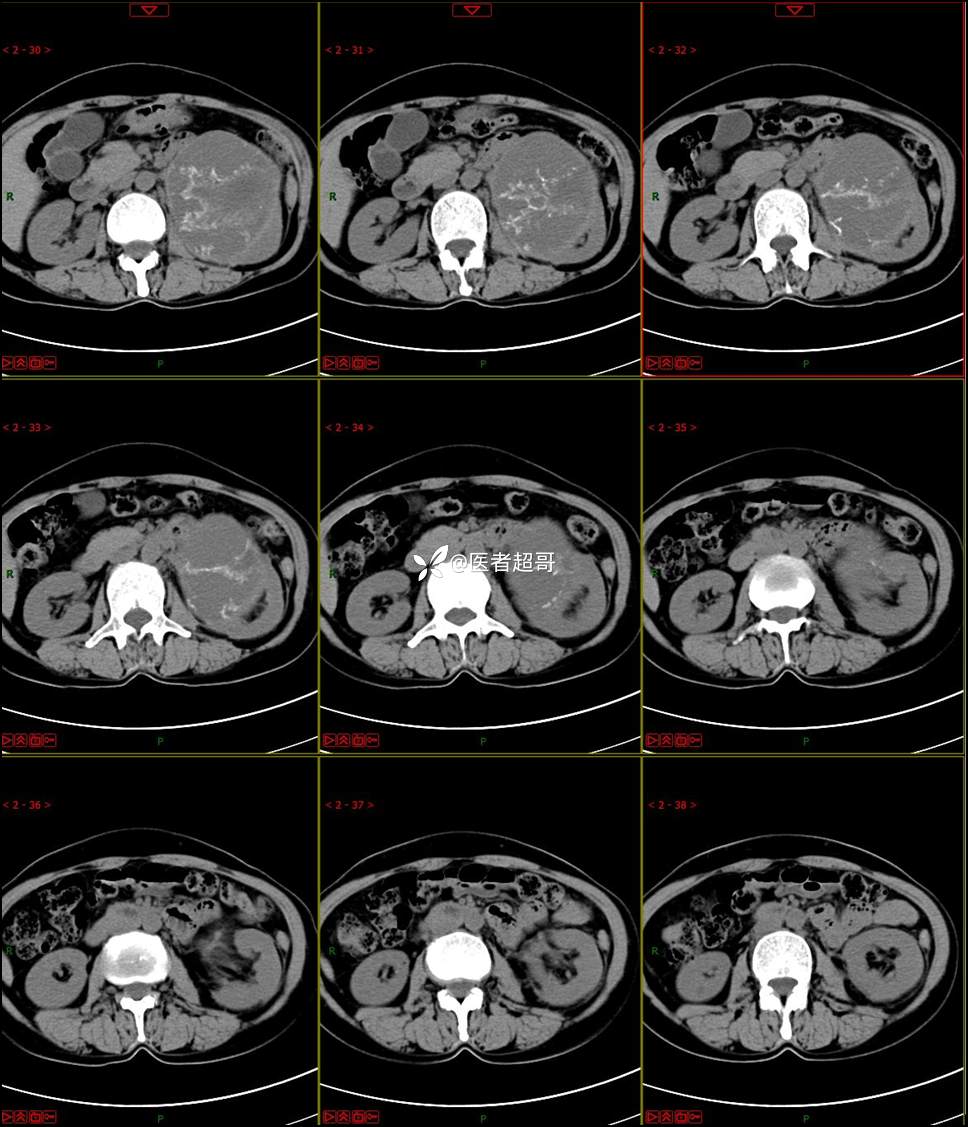

【影诊笔记768】肾脏肿瘤?肾上腺肿瘤?请诊断分析!

女 57岁 0200908 01

主 诉:发现左肾肿物7月余

现病史:患者7月前因左侧腹部疼痛不适,就诊市人民医院,行CT平扫:左侧肾上腺区混杂密度肿块,考虑肿瘤合并出血,行保守治疗后症状缓解出院,左侧下腹部及左侧髋部疼痛不适,无尿频、尿急、尿痛,无肉眼血尿,无寒战、发热,今患者为求进一步诊治,就诊我院,门诊以“左肾肿物”为诊断收入院,患者自发病以来,神志清,精神可,饮食睡眠可,小便如上述,大便正常,体重未见明显改变。